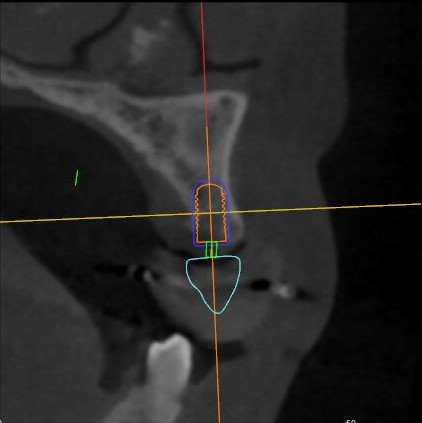

術(shù)中操作

導(dǎo)航下精細(xì)分配修復(fù)間隙,精細(xì)規(guī)劃植入方向,避開(kāi)上頜竇底,精確植入

從術(shù)后CBCT顯示可以看出,手術(shù)操作中完美地避開(kāi)上頜竇底,并兼顧了正確的種植方向和修復(fù)間隙